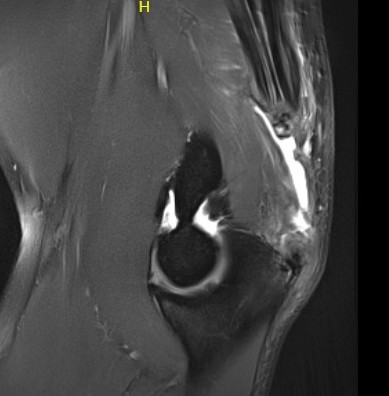

MRI